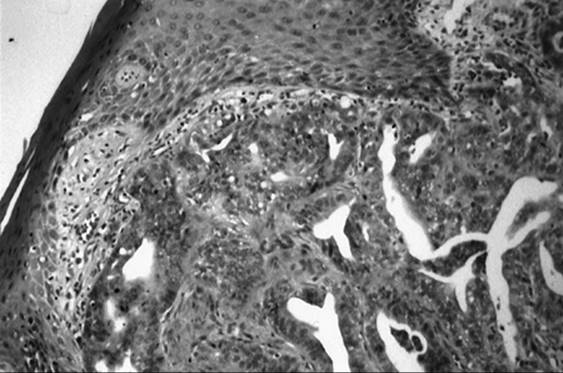

Adenocarcinoma of the vulva tends to arise in the Bartholin gland, although it may also arise from the sweat glands or Skene glands of the vulva (Fig. 51.13). Adenoid cystic carcinoma also arises from the Bartholin gland and is characterized by slow growth and a tendency for local and perineural invasion (Fig. 51.14). Distant metastasis is most commonly seen in the lung. Therapy involves radical excision, ipsilateral lymphadenectomy, and postoperative radiotherapy.

FIG. 51.13. Moderately differentiated adenocarcinoma arising from vulva.

FIG. 51.14. Adenoid cystic carcinoma arising from Bartholin gland.